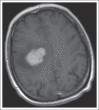

Treatment of Brain Metastases

Brain metastases (BMs) occur in 10% to 20% of adult patients with cancer, and with increased surveillance and improved systemic control, the incidence is likely to grow. Despite multimodal treatment, prognosis remains poor. Current evidence supports use of whole-brain radiation therapy when patients present with multiple BMs. However, its associated cognitive impairment is a major deterrent in patients likely to live longer than 6 months. In patients with oligometastases (one to three metastases) and even some with multiple lesions less than 3 to 4 cm, especially if the primary tumor is considered radiotherapy resistant, stereotactic radiosurgery is recommended; if the BMs are greater than 4 cm, surgical resection with or without postoperative whole-brain radiation therapy should be considered. There is increasing evidence that systemic therapy, including targeted therapy and immunotherapy, is effective against BM and may be an early choice, especially in patients with sensitive primary tumors. In patients with progressive systemic disease, limited treatment options, and poor performance status, best supportive care may be appropriate. Regardless of treatment goals, use of corticosteroids or antiepileptic medications is helpful in symptomatic patients. In this review, we provide a summary of current therapy, as well as developments in the treatment of BM from solid tumors.